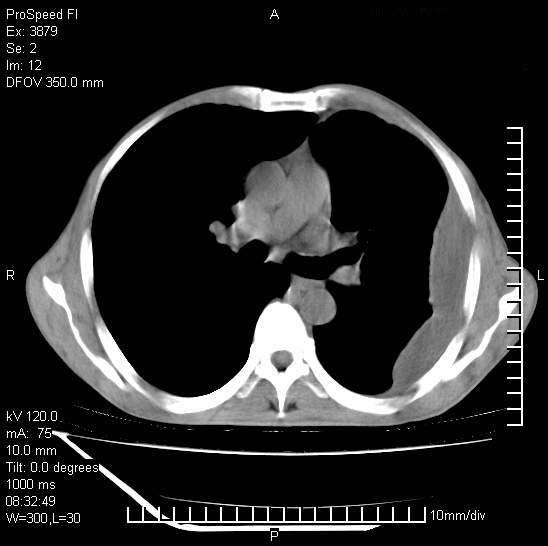

以下是引用37度在2008-6-6 11:20:00的发言:[br]1.包裹性积液,多考虑结核性;[br]2.穿刺术后改变。

以下是引用312nanyang在2008-6-6 15:12:00的发言:[br]基本支持楼主意见[br]疑问?左下肺支气管旁的软组织(16层)密度怎么解释?淋巴结还是斜裂胸膜增厚所致?能否增强进一步检查